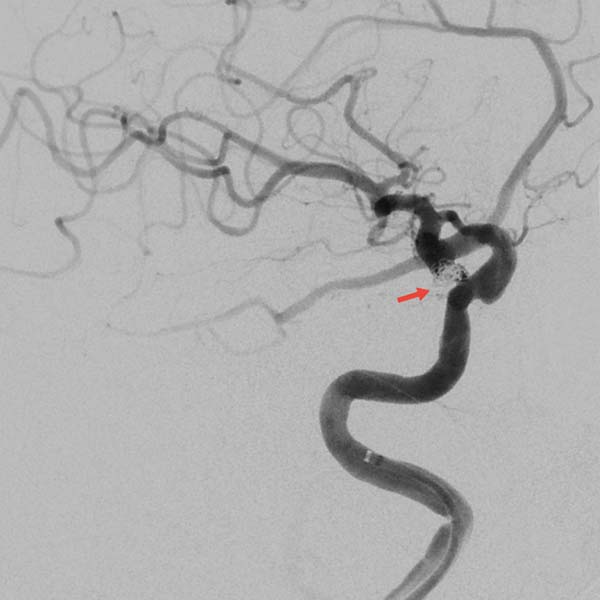

▲术后即刻造影见动脉瘤近致密栓塞

载瘤动脉及胚胎型大脑后动脉通畅